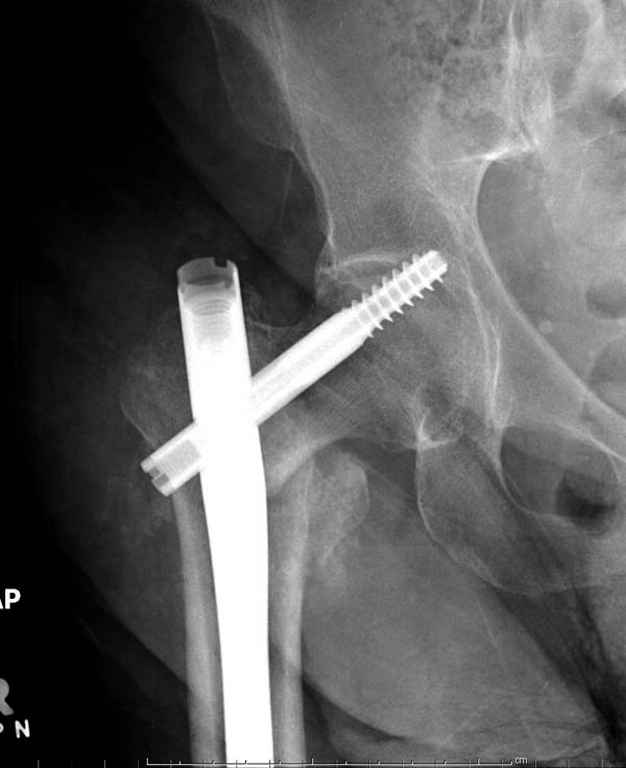

Перелом тут больше подвертельный. Нагрузка без торцевого упора на уровне перелома привела к телескопированию отломков на стержне. Ну и варус небольшой тоже свою лепту внес - если бы его не было, контактирующие латеральные стенки обоих отломков предотвратили бы укорочение, да и срослось бы за пару месяцев. А раз не срослось, упора отломков нет, более слабым местом оказались не нижние винты, а кость в головке и шейке. Так что надо было хотя бы удалить нижние винты до начала полной нагрузки.

Наверно, эндопротезирование. Есть более щадящий вариант - реостеосинтез (с устранением варуса и укорочения!), а после сращения и при наличии выраженного болевого синдрома - стандартное протезирование.

На мой взгляд, причиной телескопирования явилось несоответствие диаметра гамма нэйл с диаметром канала подвертельного отдела бедра: обратите внимание на величину протрузии шеечного винта и величину медиализации дистального фрагмента - они одинаковы, смещение или телескопирование фрагментов происходило до того момента, пока гамма нэйл не упёрся в медиальный кортекс и образовалось пространство между латеральным

кортексом и латеральной поверхностью гвоздя.

В данном случае в головке бедра и в вертлужной впадине огромный дефект, навряд ли удалением импланта или заменой на другой можно сохранить сустав.

Здраствуйте. По данному снимку видно 2-а основных момента которые привели к протрузии винта в вертлужную впадину: 1) шеечный винт дистальной поверхностью наружнего края "зацепился" за латеральный кортикал бедра, это не дало сработать динамической системе гвоздь-винт. 2) лучьше шеечный винт проводить ближе к дуге Адамса, там болееплотная костная ткань. Решенее: как подготовка к эндопротезированию, реостеосинтез, можно такой же системой, но с учетом упомянутых моментов, максимальное безнагрузочное ЛФК (без боли).